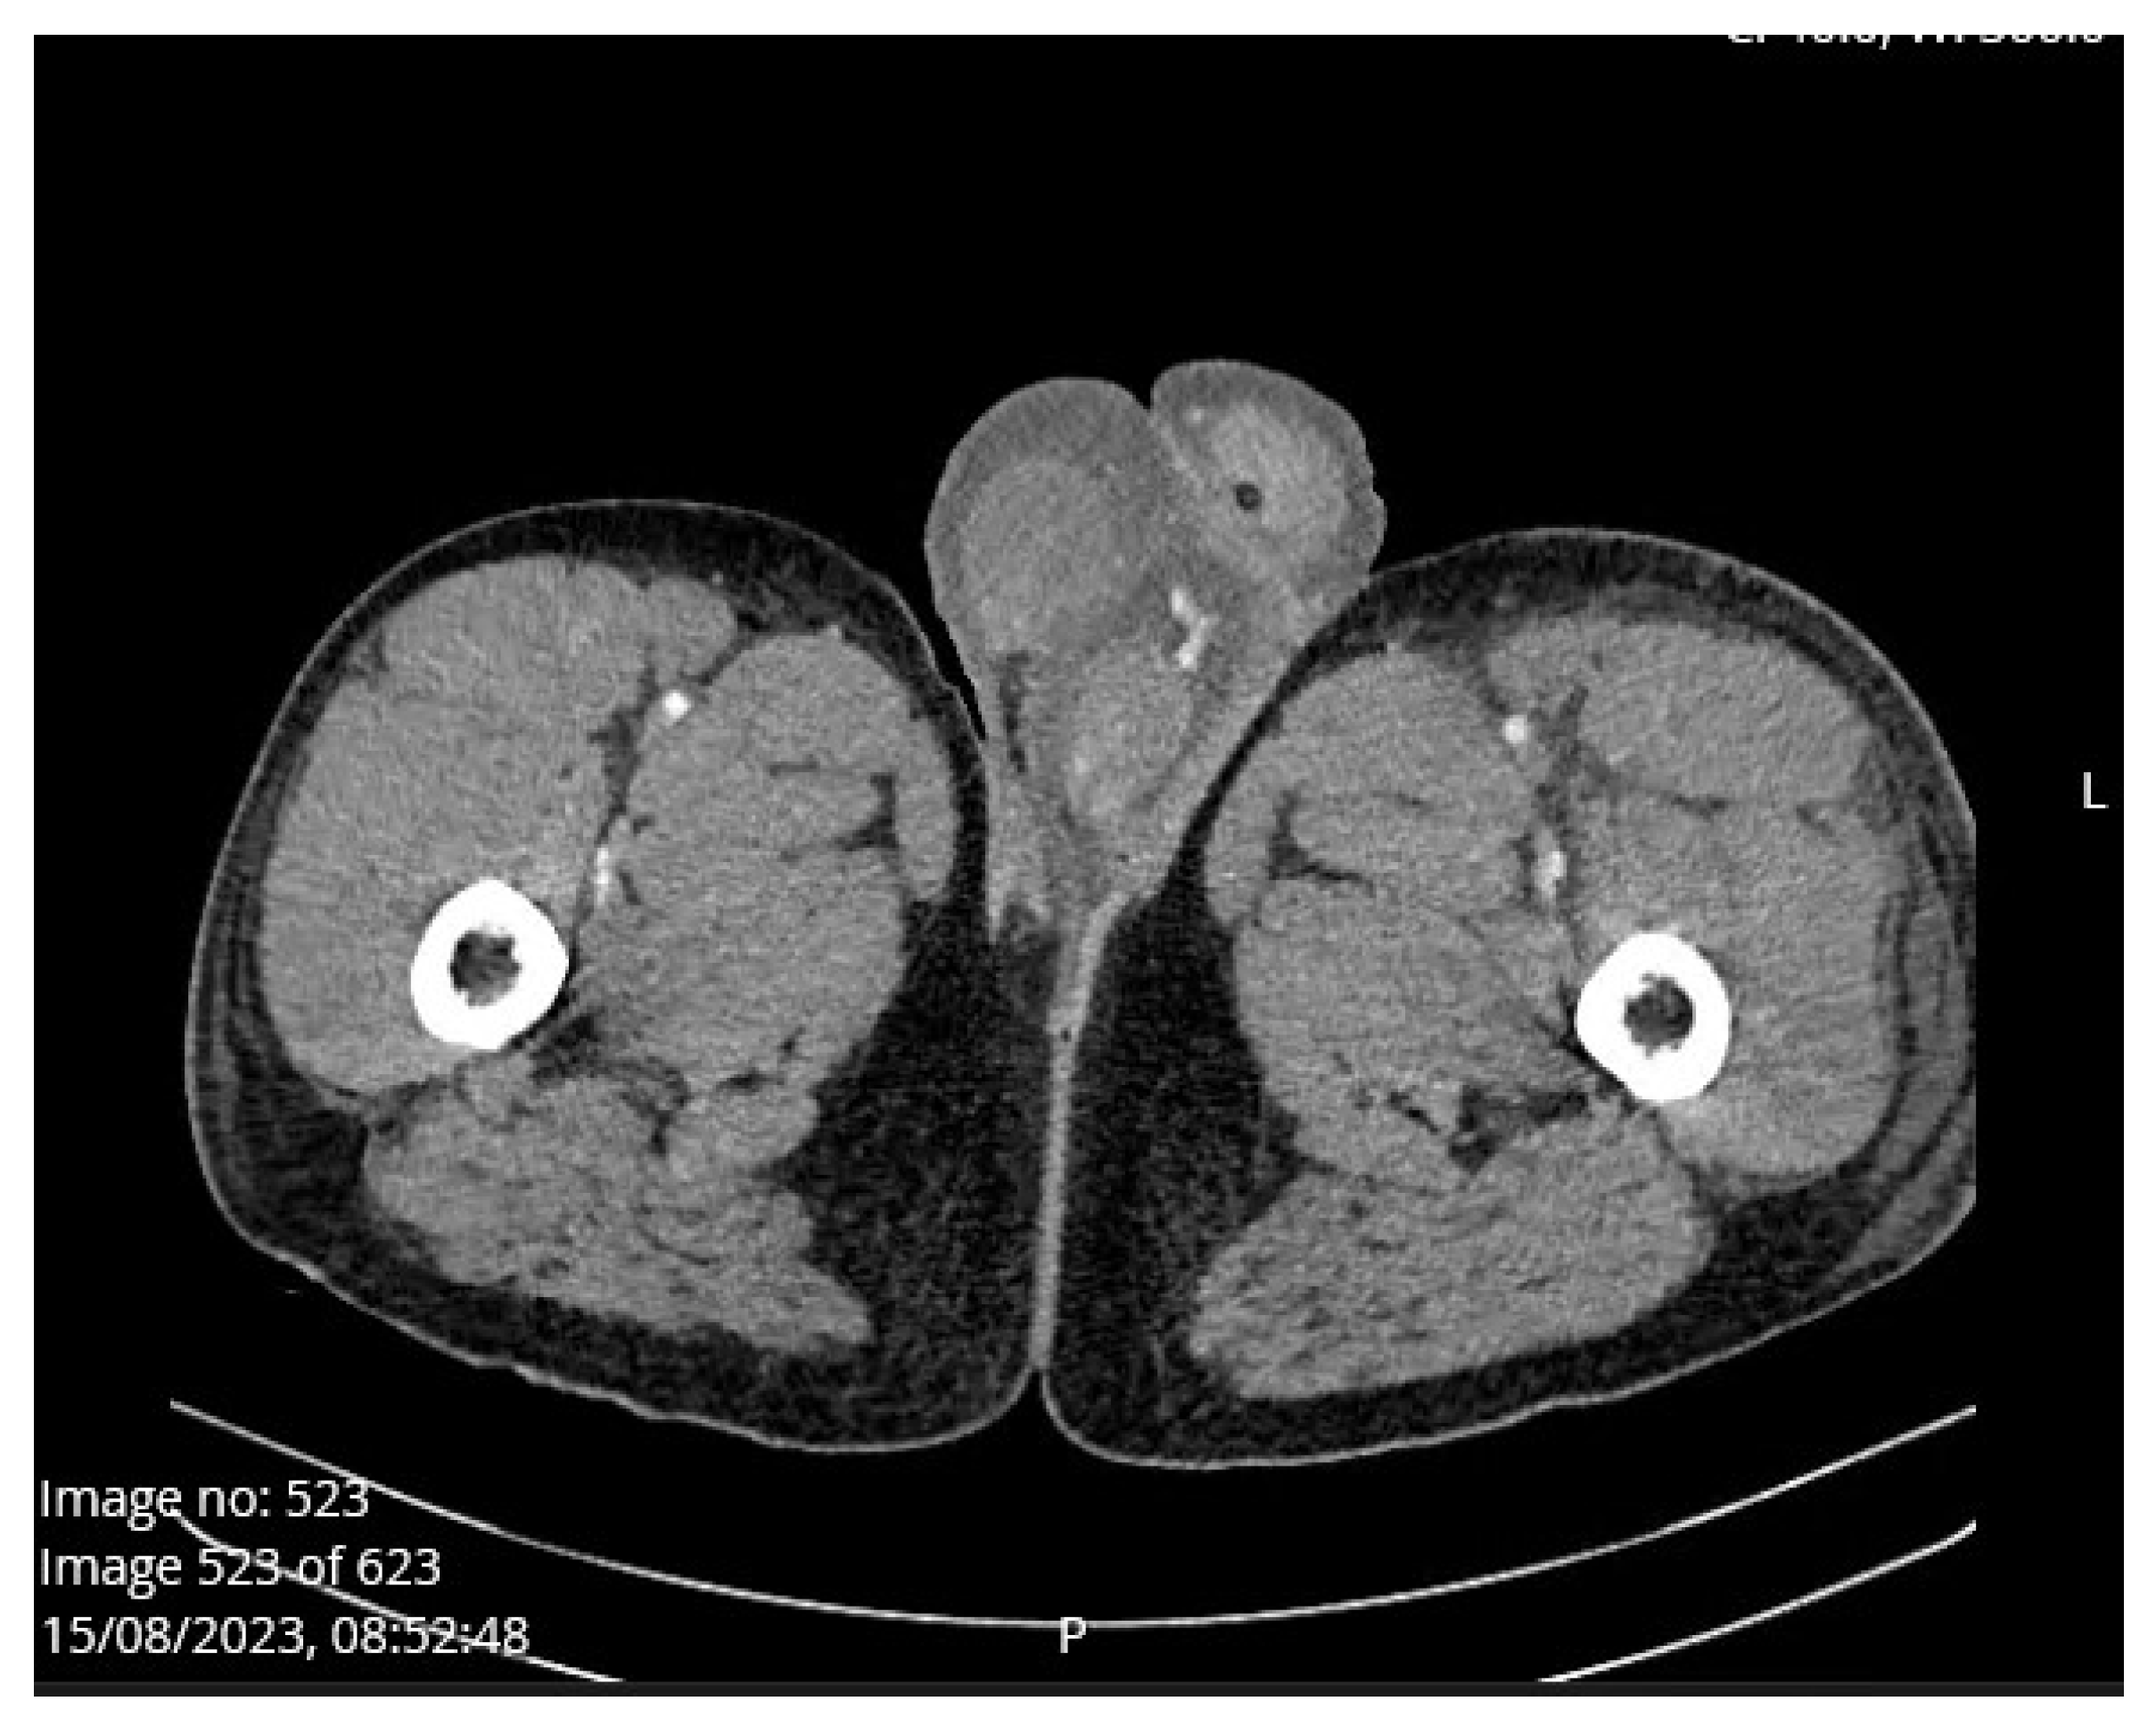

Case Presentation